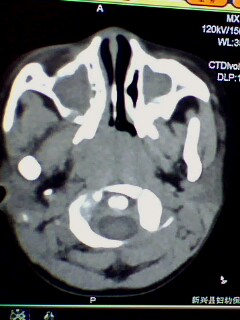

标题: PED3023:鼻咽增殖体肥大。

男,3岁小儿,经常睡觉时张口呼吸、打鼾。

1、鼻咽增殖体肥大继发左侧乳窦炎?

2、双侧上颌窦炎?

腺样体肥大,右侧扁桃体炎,双侧上颌窦炎症(鼻窦炎)

1)鼻咽腺样体肥大。2)双侧上颌窦、双侧筛窦及双侧蝶窦炎症。